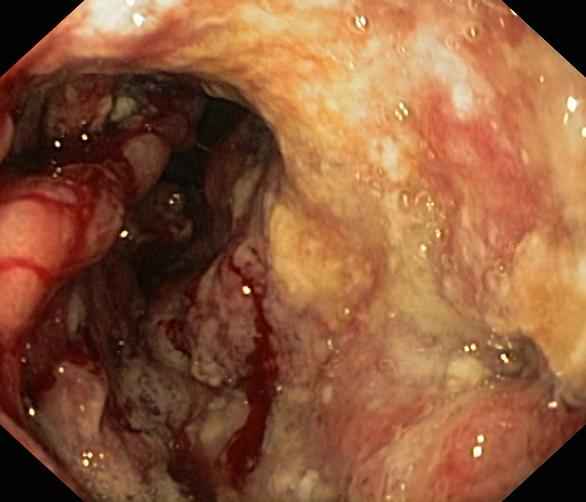

Krwawienie

Nowotwory przewodu pokarmowego